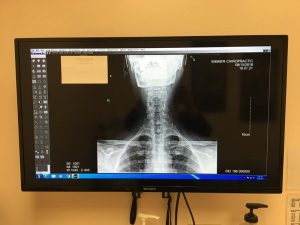

Chiropractic radiology is a specialized aspect of chiropractic care. It is a technique and diagnostic tool that we use to look inside the body in a completely non-invasive way. X-rays allow us to create an image of the skeletal system, thereby providing chiropractors with a better understanding of your body.